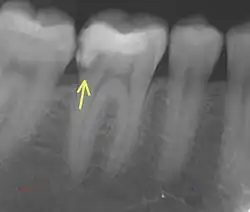

7. Radiographic examination

a. Periapical Radiographs

These provide detailed 2D images of the tooth and can detect fractures extending into dentin but may miss subtle enamel-only cracks due to their limited resolution.

b. CBCT

CBCT offers 3D imaging with high spatial accuracy, ideal for locating and assessing fractures extending into dentin or adjacent structures.

c. Micro CT

MicroCT has a high detection accuracy, capable of identifying cracks with widths ranging from a few tenths to tens of microns. It is widely regarded as the gold standard for detecting cracks in research on cracked teeth.